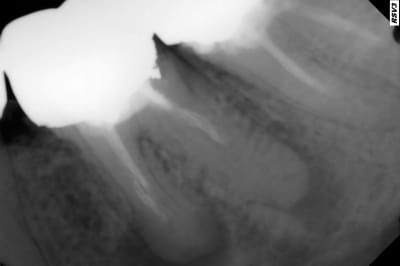

Pas mis la digue pour ce RTE c'est grave docteur ? -)

y'a un espace entre ton tenon et la gutta!!!

C'est vrai ca, avant il n'y avait pas d'espace. -)

pas de digue non plus

mais faut deviner laquelle est avant laquelle est après lol

Aucune idée fait en 2013 et revu en 2017 couronne pétée.

Mais oui, tu ne te souviens pas, tu n'étais pas encore accroc à l'Inlay-Core ... ;-))) C'est pour ça qu'elle s'est barrée ...